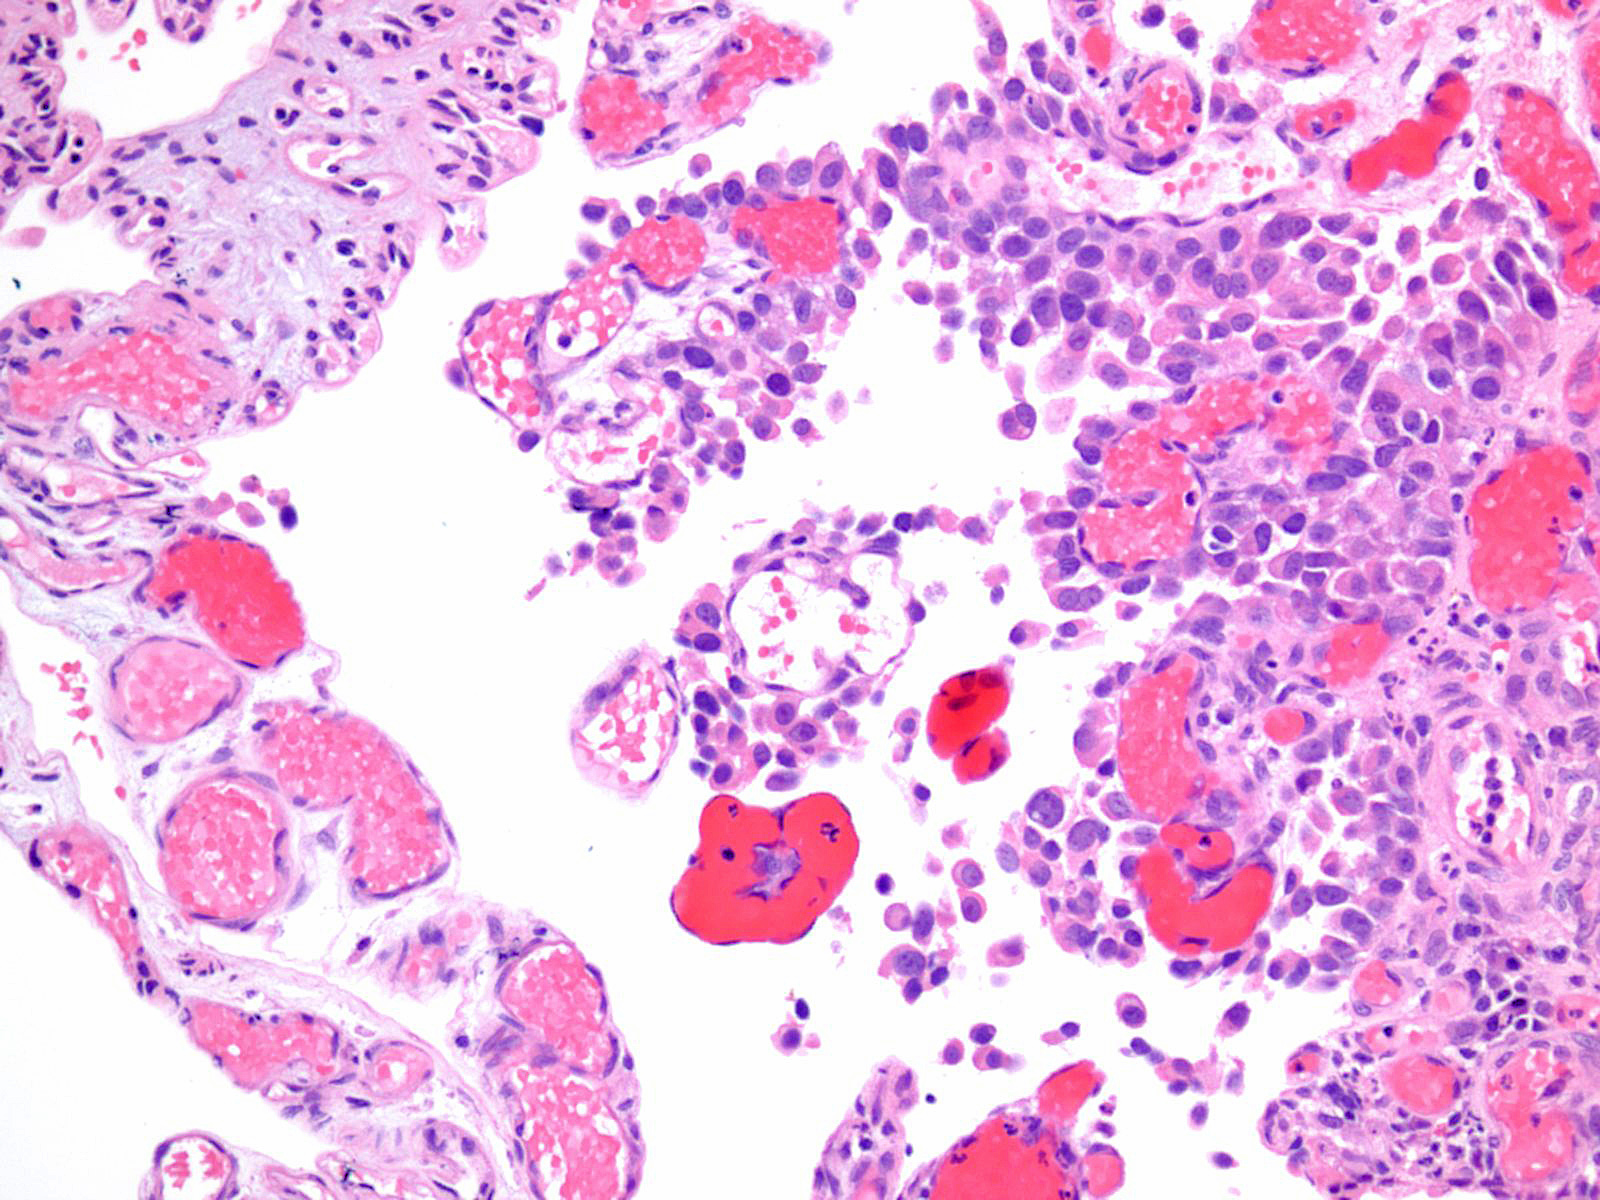

Consensus grade: High-grade papillary urothelial carcinoma (HG-PUC)

HPUC with sloughing |

Case description (by case creator):

Lesion shows marked denudation. The cells lining the papillary fronds depict marked variation in nuclear size, shape and chromatin. Cells appear loosely cohesive and the architecture is disorganized.